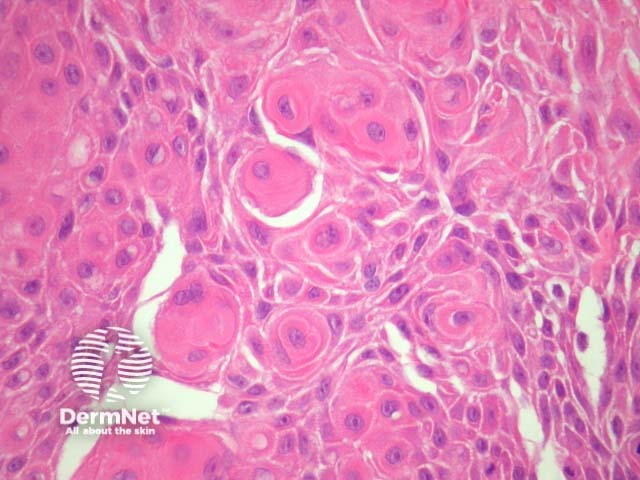

Sections show a cyst in the dermis with a proliferating epidermal component (figures 1, 2). Characteristically, the proliferative areas are made up of bland squamous epithelium with striking squamous eddies (figures 2, 3, 4). These eddies are whorles of maturing squamous epithelium and are exactly the same as those seen in irritated seborrheic keratoses or inverted follicular keratoses.

Figure 3

Figure 4